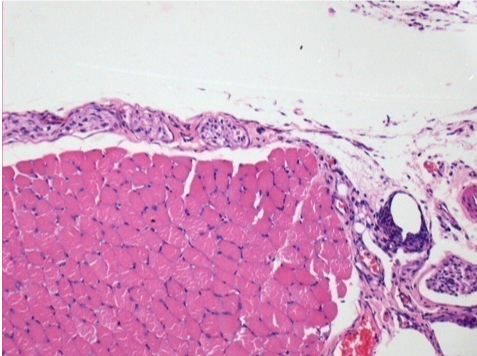

Iniezione Endopeel nel tessuto subcutaneo SC

Scatola 6

0.5 ml ( 5x 0.1ml): Iniezione SC di Endopeel nel tessuto pretibiale subcutaneo SC destro (Dx).

Sx:200x-Controllo-SC

Dx-Giorno10-SC-200X

Dx-Giorno30-SC-200X

Dx-Giorno90-SC-200X

Dx-Giorno210-SC-200X

Dx-Giorno210-SC-400X

Endopeel induce una miofibrolisi selettiva reversibile e una risposta infiammatoria approssimativamente nel periodo di 1 mese.

I cambiamenti dei tessuti muscolari sono quasi completamente reversibili.

Il muscolo é il posto migliore per iniettare Endopeel ,per la sua maggiore efficacità, il controllo e la durata della sua azione.

Nessuna necrosi ne ascesso sono stati osservati durante la sperimentazione.